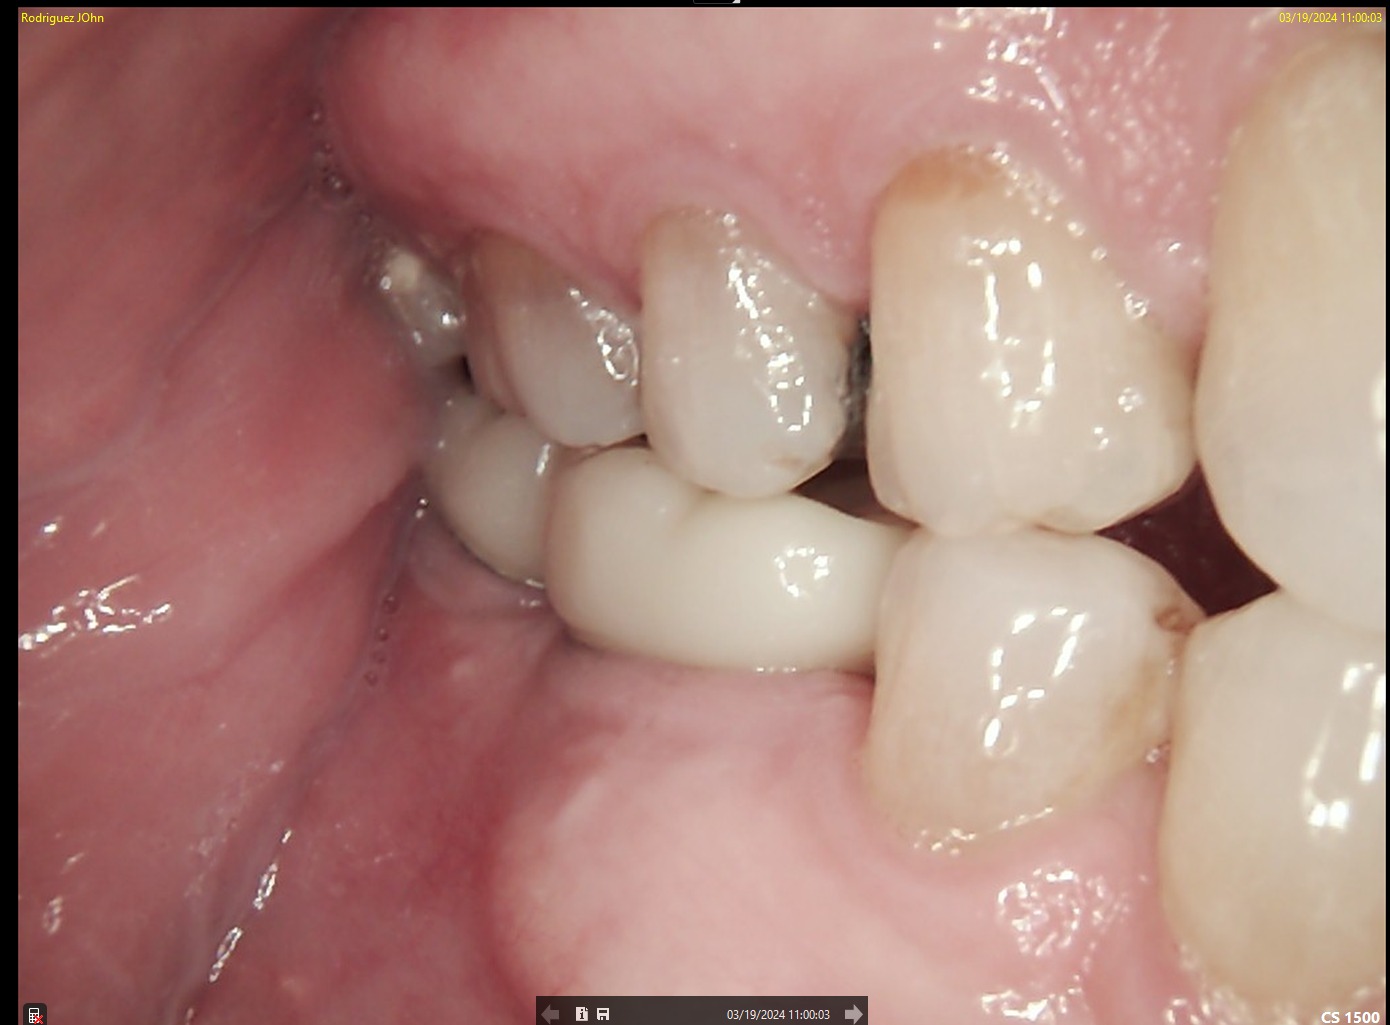

FOLLOW-UP - 2024

One-year follow-up evaluation showed:

• Stable peri-implant soft tissue contours

• Absence of inflammation or recession

• Radiographically preserved crestal bone levels

The implants remained fully functional with excellent tissue response.